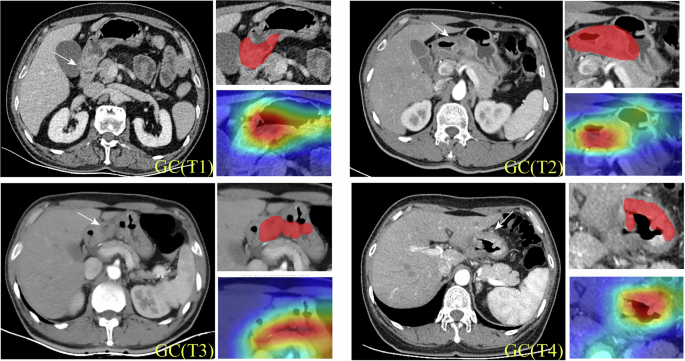

Grad-CAM heatmap visualization

To enhance the clinical interpretability of the GTRNet attention mechanism, we employed Grad-CAM heatmaps to visualize the regions of interest (ROIs) that the model prioritizes. As illustrated in Fig. 3, warm colors such as red and yellow indicate higher model attention, with increasing color intensity corresponding to greater focus; conversely, cooler colors such as blue and green represent lower attention, with darker shades indicating reduced focus. When compared with the ROIs (red-filled areas) manually annotated by radiologists, the attention distribution generated by GTRNet demonstrated a high degree of spatial overlap with expert annotations. For example, in T1-stage lesions, the heatmap predominantly highlighted the inner layers of the gastric wall, indicating that the model effectively captured imaging features associated with superficial submucosal infiltration. In contrast, for T4-stage lesions, the model’s attention extended beyond the thickened gastric wall to include the interface between the tumor and adjacent organs, suggesting its ability to detect radiological signs of tumor invasion into surrounding structures. These findings further confirm that GTRNet possesses strong interpretability and clinical relevance in the T staging of gastric cancer.

For representative T1–T4 cases, portal-venous CT images (left) and color heatmaps (right) highlight mucosa (cT1), muscularis propria (cT2), serosal surface (cT3), and pancreatic invasion (cT4).

To further quantify the spatial alignment between the model’s attention regions and the actual tumor locations, we binarized the Grad-CAM heatmaps and computed the Dice similarity coefficient by comparing them with the gold-standard masks manually segmented by radiologists. The Dice coefficients across different T stages were as follows: 0.56 for T1, 0.59 for T2, 0.60 for T3, and 0.63 for T4, indicating moderate to substantial spatial overlap between the model’s attention maps and the ground truth lesion areas. These findings suggest that the attention mechanism of GTRNet does not erroneously focus on image artifacts or non-pathological regions, but rather accurately identifies key anatomical structures that are critical for T staging. Furthermore, in Supplementary Fig. 1, we illustrate several representative misclassified cases to investigate potential error patterns under conditions of ambiguous staging boundaries or complex anatomical configurations. This analysis provides insights that may guide future improvements in model performance.